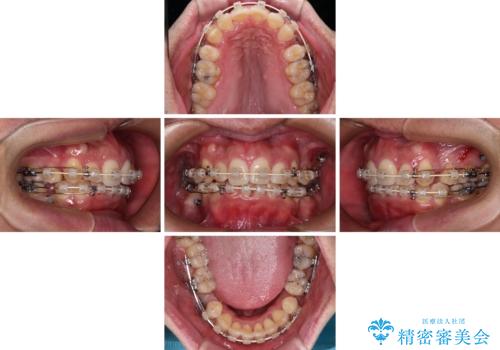

- 矯正装置

- 審美装置

上顎歯列幅を側方に拡大するとともに、歯列全体を後方に移動させるためのアンカースクリューと補助装置を使用し、上顎左右第一小臼歯2本、下顎左右第二小臼歯2本、計4本を抜歯し、ワイヤー装置にて矯正治療を行うこととしました。